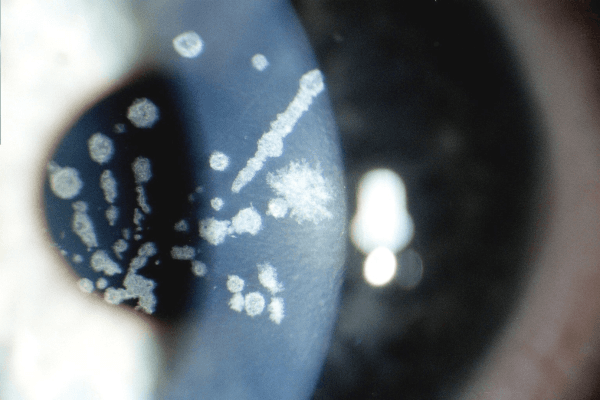

Loạn dưỡng dạng hạt

Bệnh thường xuất hiện ở trẻ nhỏ dưới 10 tuổi nhưng chủ yếu biểu hiện rõ rệt khi trẻ ở độ tuổi trưởng thành. Biểu hiện thành sự lắng đọng chất màu trắng ở nhu mô giác mạc trung tâm, kích thước khác nhau và phân tách rõ, cách nhau bởi những khoảng trong suốt như vụn bánh mì xen kẽ.